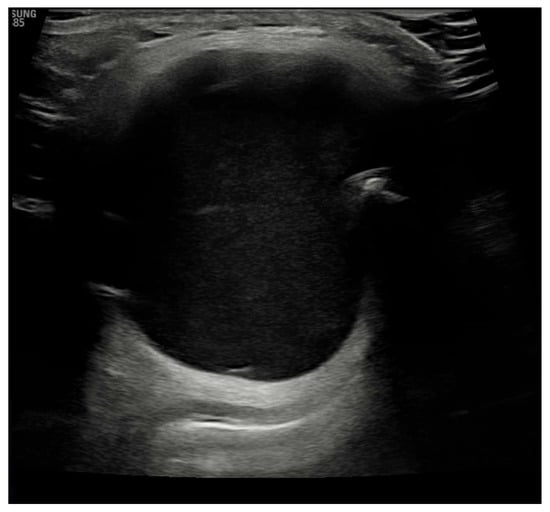

Laboratory results showed that the patient was euthyroid, and his anti-thyroid peroxidase (anti-TPO) was negative. Ultrasound imaging showed an echogenic, homogeneous thyroid with a total volume of 7 mL, with no intra-thyroid nodules. It also showed a mass above the thyroid gland, slightly to the right of the midline. The mass was approximately 0.041 m × 0.044 m × 0.033 m with a strong connective tissue capsule and an anechoic internal structure, as shown in Figure 2.

Figure 2.

Ultrasound image showing echo-normal and homogeneous thyroid gland.

There are several methods for diagnosing a TGDC, including ultrasound imaging of the neck, an appropriate and non-invasive procedure. Preoperative fine-needle cytology is also a cheap and safe method [24]. Ultrasound imaging of our patient showed an echogenic, homogeneous thyroid with a total volume of 7 mL, with no intra-thyroid nodules. It also showed a mass measuring 0.041 m × 0.044 m × 0.033 m above the thyroid gland with a solid connective tissue capsule and an anechoic internal structure.